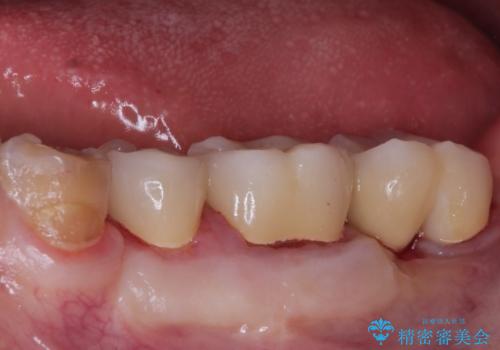

今回の症例は遠心根を保存するメリット・デメリットを患者さんと話し合い、治療を進めております。

条件が少しでもよくなる様に、再生治療および確定外科を行い良好な歯周状態でオールセラミッククラウンを装着しております。